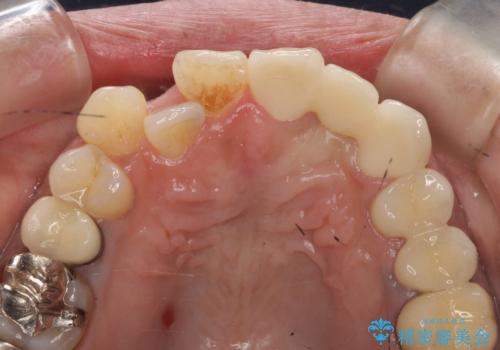

- 左上2番目の歯がグラグラするので診て欲しいといらっしゃった方の症例です。

左上2番目の歯は歯根が破折してため抜歯し、左上123のブリッジによる欠損補綴を行いました。

左上4、5番目の歯は根尖病変を認めたため再根管治療を行い、オールセラミッククラウンによる補綴を行いました。

なお左上4に関しては縁下歯質を改善するため、歯冠挺出を行っております。